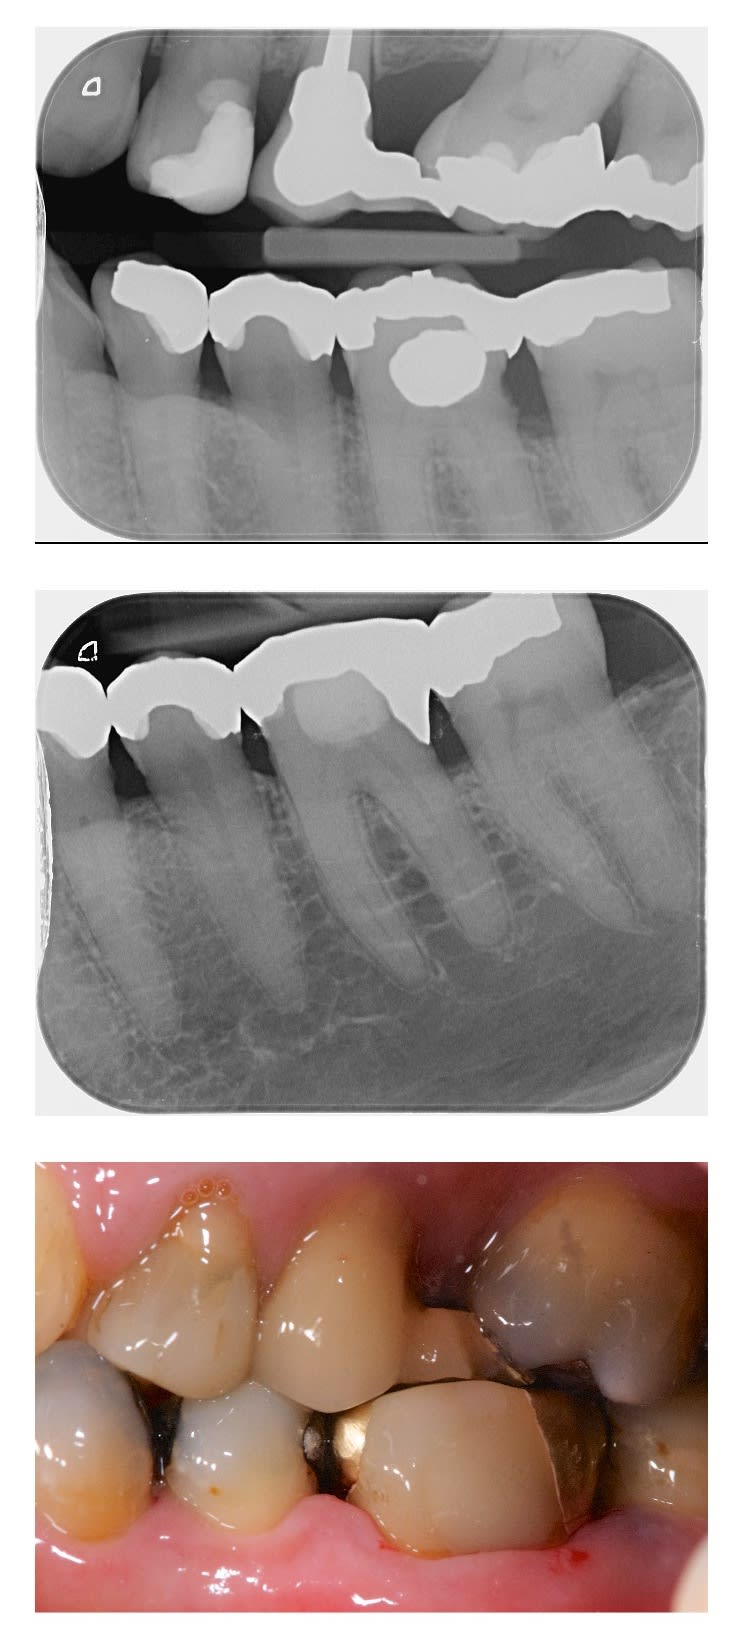

Quoi faire pour la 36?

Le cas est déjà traité. Mais c'est intéressant de confronter nos avis.

couronne ou onlay effectivement, en fonction de la perte de substance.

Si pas possible de diguer, onlay metal.

En vestibulaire , c 'est un amalgame ?

Oui transformé en composite le jour de l'empreinte.

Heureusement que c'est le désert en antagoniste ,

Parce les cuspides d'appui sont fragilisées .

C'est vrai qu'en revoyant les photos j'aurais pu/dû faire un recouvrement cuspidien.

Crown and Bridge (oxyphosphate de zinc). Classic quoi.